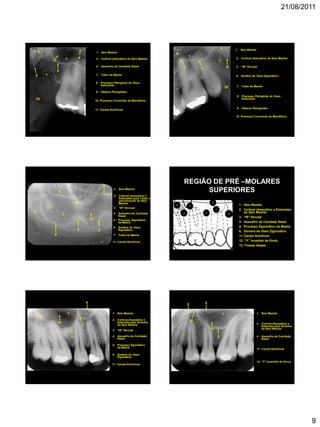

REGIÃO DE PRÉ –MOLARES

SUPERIORES

1. Seio Maxilar

2. Cortical (Assoalho) e Extensões

do Seio Maxilar

3. “W” Sinusal

4. Assoalho da Cavidade Nasal

5. Processo Zigomático da Maxila

6. Sombra do Osso Zigomático

11. Canais Nutritivos

12. “Y” Invertido de Ennis

13. Fossas Nasais

4

2

5

1

6

3 12

5. Processo Zigomático

da Maxila

3

2. Cortical (Assoalho) e

Extensão para Alveolar

6. Sombra do Osso

Zigomático

4. Assoalho da Cavidade

Nasal

11

12